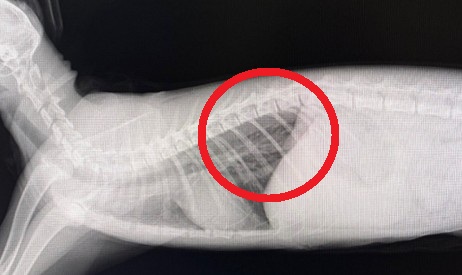

胸腔に胃が入り込んでいるのを確認

胸腔内に胃が入り込んでしまっているのが分かります。

その後は開腹部も縫合し、終了です。                                           翌日に確認のレントゲンを撮り再発がないか確認したのが下の写真です。綺麗に胃が腹腔内に収まっているのが分かります。